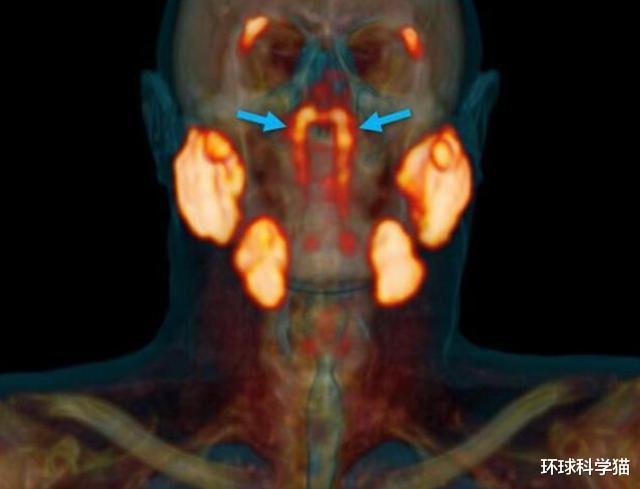

这是一个什么器官?确实 , 在人类科学发展到如今的阶段 , 对人类身体的研究可以说已经非常透彻了 , 多少器官 , 多少骨头等等都是一清二楚 , 而这次的研究是来自荷兰科学团队 。 根据科学报告指出 , 这次发现的器官是位于在鼻腔和喉咙交汇的角落里 , 是一组可能之前未被确认的器官 。

如果得到了证实 , 这意味着这是大约三个世纪以来首次发现这样的腺体 , 所以让科学家感到惊讶 , 上面我们也说了 , 隐藏很好 , 所以才这么难发现 。

如今这个发现结果在《放射治疗与肿瘤学》(Radiotherapy and Oncology)杂志登刊 , 他们发现之后肯定就是由国际科学团队去证实 , 所以我们只需要等待结果 。 大家都知道 , 在任何一本现代解剖学书籍中 , 都会介绍唾液腺有三种主要类型 , 但是如今的这个结果可能颠覆了这种说法 , 可能是存在第四种唾液腺 。

根据美国病理学家瓦莱丽·菲茨休表示 , 这项研究的规模较小 , 可能还不足以证明所有人都有这种情况 , 所以可能还要加大规模才行 。 当然这个发现也有人表示不赞同“新器官”的说法 , 因为除了已知的三组大唾液腺外 , 在人体的口腔和喉咙内壁上上 , 还散布着大约1000个的小唾液腺 。 它们更加“娇小” , 更难以通过成像或扫描找到 。 所以到底如何定论 , 如今还没有精确的说法 , 这就是大概的情况 。